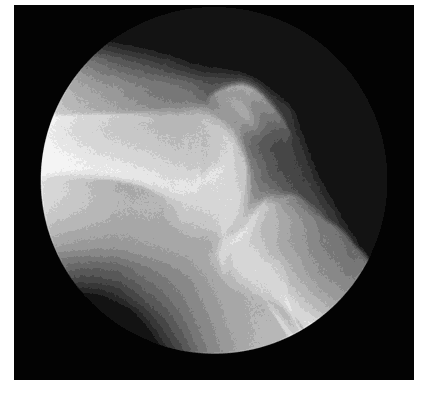

多见于儿童及青年,以急性发热及关节肿痛起病。主要侵犯大关节,如膝关节、踝关节、腕、肘、肩等关节,关节红肿热痛,呈游走性,一处关节炎症消退,另处关节起病。关节炎症消退后不留永久性损害,X线关节摄片骨质无异常,血清类风湿因子阴性,抗链球菌溶血素、抗链激酶及抗透明质酸酶阳性。

手部关节X线片改变(表现为关节及其邻近骨质疏松或明显的脱钙现象,关节间隙的狭窄)。

以下肢负重关节。如髋关节和膝关节发病最多,不对称,多为单关节炎。关节腔穿刺液呈化脓性改变。涂片或培养可找到细菌。X线关节摄片可见关节局部脱钙、骨质侵蚀及关节间隙变窄。易并发骨膜炎及骨髓炎。